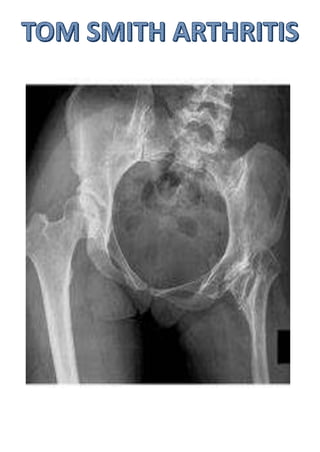

Septic arthritis of hip in infancy.

Results in complete destruction

of cartilaginous femoral head.

Presentation is a child in his

preschool age with painless limp.

Affected limb is shorter.

X ray shows complete absence of

head and neck of femur.